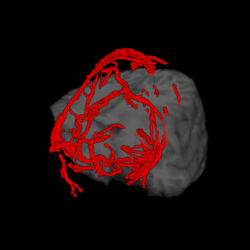

A major task is to implement the abstraction layer for rendering synthetic data, independent of display technology. This may involve use of the MNI's VTk-based IGNS system (IBIS) or build on our own rendering architecture, with low-level rendering engines for each display type, and input taken from existing neuro-visualization tools. In either case, the goal is to integrate the 3D rendering of MRI, fMRI, PET, DTI, and intra-operative ultrasound data, possibly in conjunction with the tracked position of surgical tools, and add modules for additional processing (e.g., feature highlighting, density control, and interactive manipulation/deformation). Rendering strategies must take into account the importance of merging volumetric and surface rendering techniques when dealing with the multiple data sets available.

| cutting plane + MRI | cutting plane + blood vessels | blood vessels + fMRI + PET | blood vessels + fMRI + PET + MRI |

The experimental task was to define a straight vessel-free path from the cortical surface to the targeted tumor using (a pen-like) probe. Because of the complex anatomical structure of the human brain and the topology of key blood vessels, defining such a path for insertion of probes and tools can be a challenging task in practice. For this task, we visualized the segmented brain vasculature with a simulated tumor at positions of varying difficulty of reaching, as shown in Figure a. Subjects were provided with hand-coupled motion cues as they manipulated the volume and probe (Figure b)). Two tangible objects were used as input devices: a small plastic skull to manipulate the orientation and proximity (zoom) of the vasculature, and a replica of a biopsy probe used to locate the tumor. Once the subject was satisfied with the probe position, a foot step, sensed by an electronic game controller dance pad, is used to end the trial. This avoided the risk of introducing jitter to the probe position, which may have resulted otherwise had a manual button press been required.